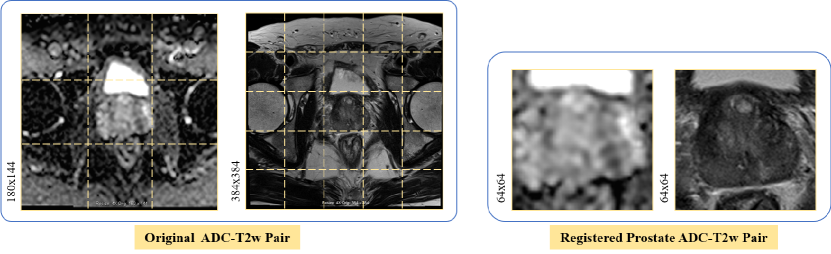

III-B Data Preprocessing for Training and Testing

For these two datasets, a radiologist manually selected 533533533 original ADC-T2w pairs containing CS PCa lesions and 199219921992 ADC-T2w pairs which are nonCS PCa cancerous. The selection criterion was that both CS PCa lesions and prostate glands were clearly visible. For each selected ADC-T2w pair, we cropped and aligned the prostate region using an automated prostate detection and registration method proposed in [6]. As shown in Fig. 5 (left), the original sizes of ADC and T2w are 180×144180144180\times 144 and 384×384384384384\times 384 respectively, and the width of the entire image is around 333 and 555 times of the width of the prostate region in ADC and T2w respectively. Therefore, we first resized the ADC-T2w pairs to the same size of 256×256256256256\times 256 as the input to the automated detection and registration method, and then set the output image size of the automated detection and registration method to 64×64646464\times 64 for better preserving useful information of the prostate in mp-MRI data. The exemplar output of the processed prostate ADC-T2w pair is shown in Fig. 5 (right).

Refer to caption

Figure 5: An example of original ADC-T2w pair (left) and its corresponding registered and cropped ADC-T2w pair of prostate region (right).

The processed prostate ADC-T2w pairs, with a total of 252525252525 pairs, were randomly divided into the TrainSet (483483483 CS and 194219421942 nonCS pairs) and the TestSet (505050 CS and 505050 nonCS pairs). Each patient’s data is either solely in the training or solely in the test set, but not both, to avoid overfitting data of specific patients.